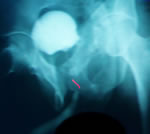

- Обзорная и экскреторная урография - функция верхних

мочевых путей не нарушена, камень мочевого пузыря,

деформация костей таза.

- Восходящая уретрография - подозрение на стриктуру

перепончатого отдела уретры.

- Микционная уретрография - дилятация простатического

отдела перепончатой уретры